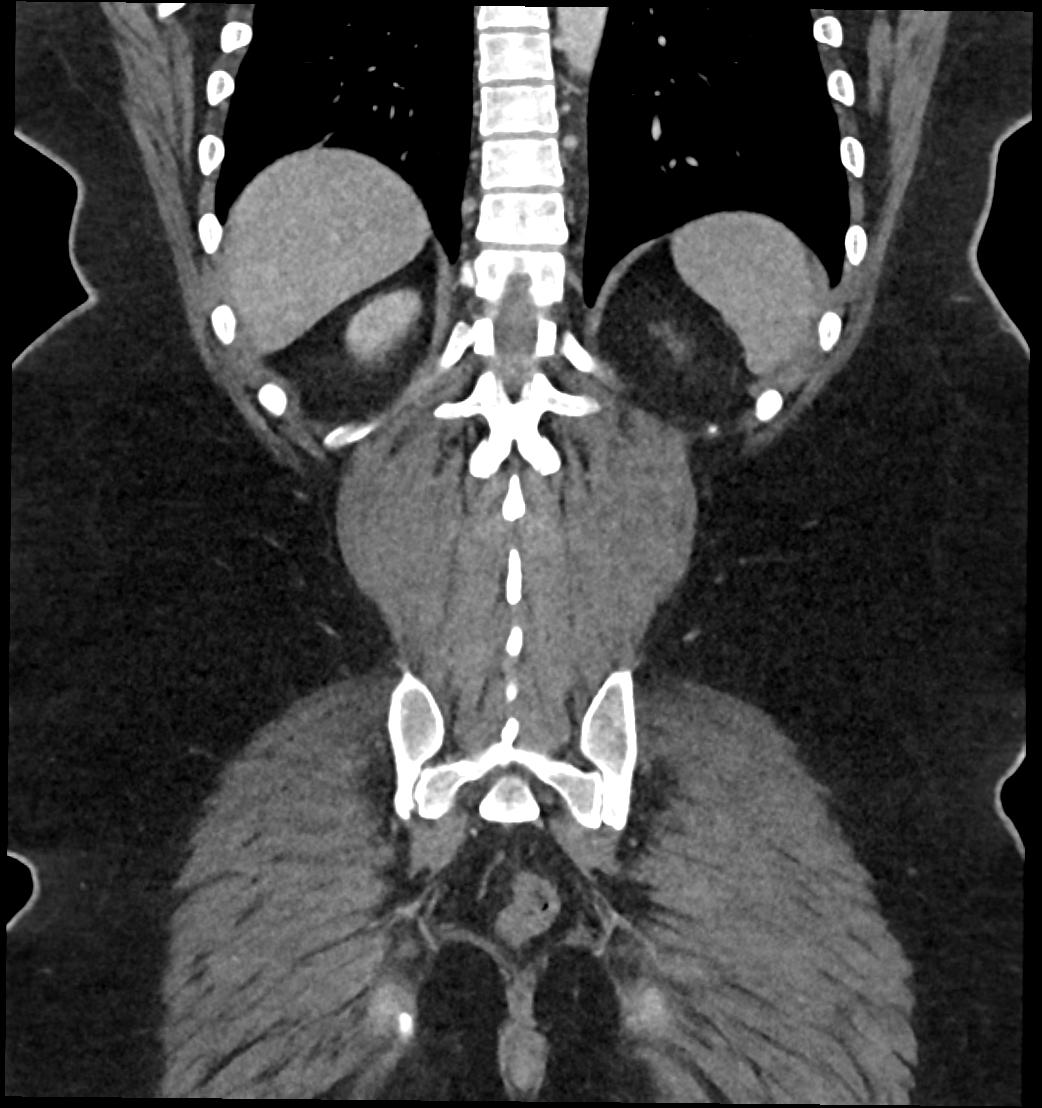

Patient: Padmakumar A. , *1988-04-24, PID: 3000069741773230809

Study Description: CT ABDOMEN

Image Series: Abdomen Cor 3mm [4]